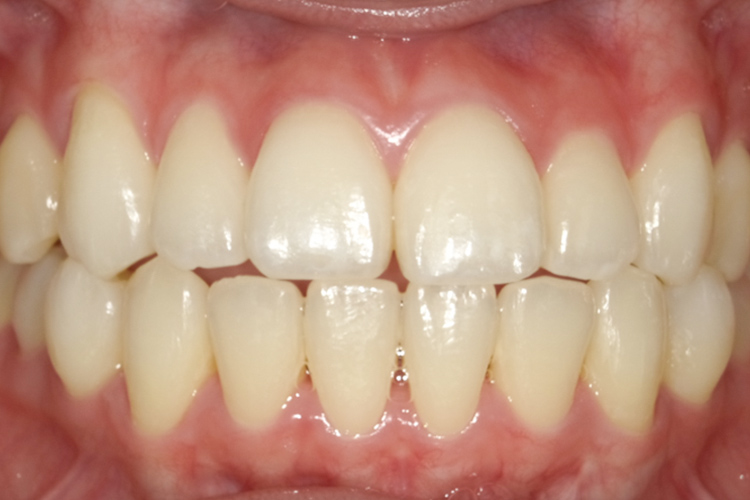

治療前

治療後